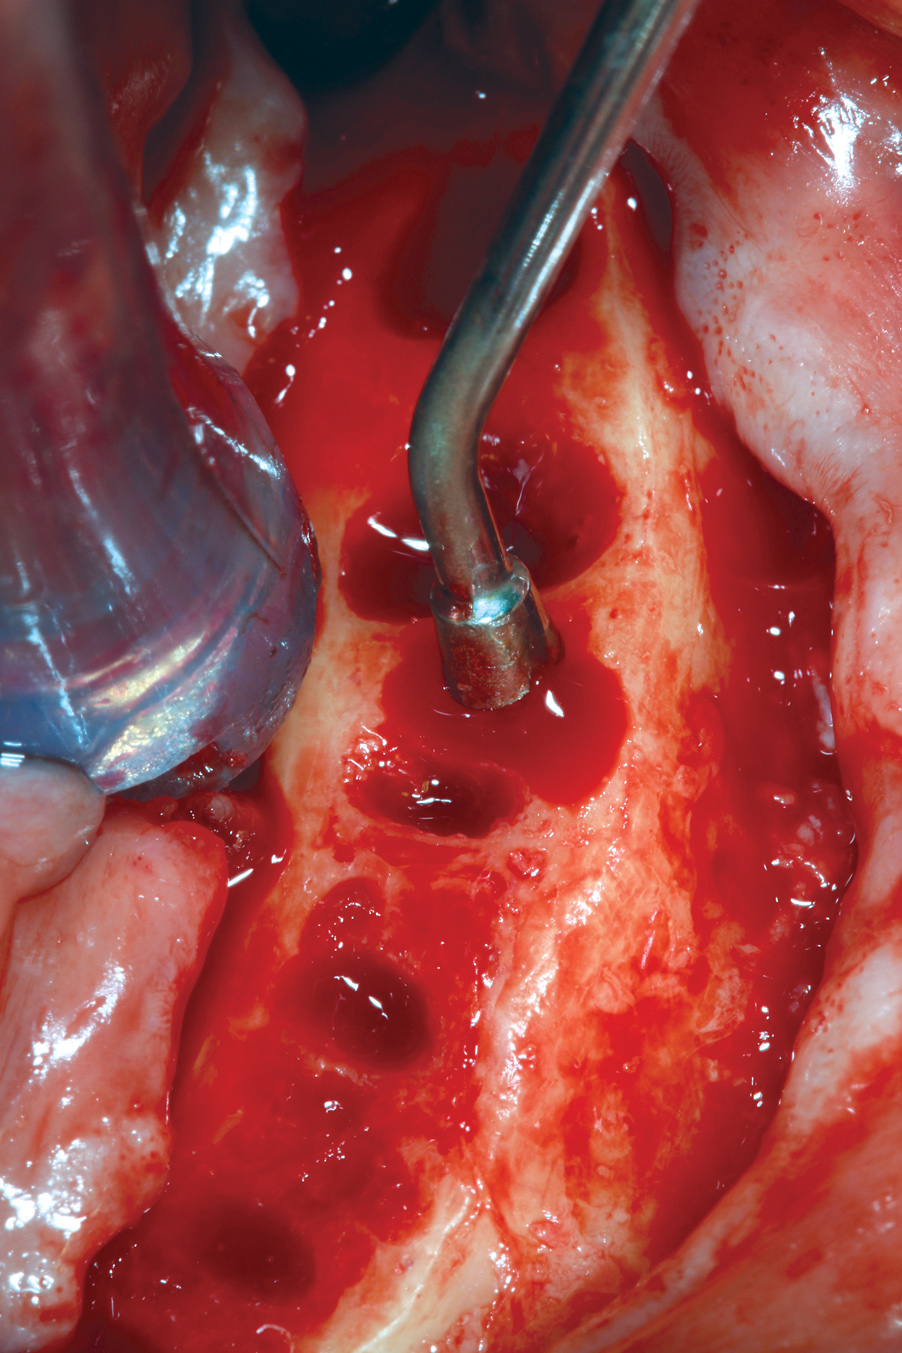

Fig 9. Alveolar bone reduction prior to dental implant placement in a mandibular All-on-4–style dental implant surgery.

Figure 9

Hemorrhage From Osseous Nutrient Canals

All-on-4–style treatment typically involves reduction of alveolar and/or basal bone (Figure 9) to achieve adequate restorative space for both the interim and final prostheses.25-27 During reduction of this bone, exposure of intraosseous nutrient canals28,29 may lead to hemorrhaging that may obscure visualization of the surgical field. If left uncontrolled, hemorrhaging from nutrient canals can become significant, resulting in excessive blood loss. It is not uncommon to encounter multiple concurrently hemorrhaging intraosseous nutrient canals, especially during mandibular bone reduction.

When faced with this situation, the author uses the blunt end of a handheld instrument, such as a Woodson instrument (Figure 10), to put heavy pressure on bone directly adjacent to the bleeding nutrient canal. This pressure typically deforms the adjacent bone to a point at which it occludes the hemorrhaging. The author has encountered hundreds of hemorrhaging intraosseous nutrient canals and has never had this technique fail to achieve the desired results.